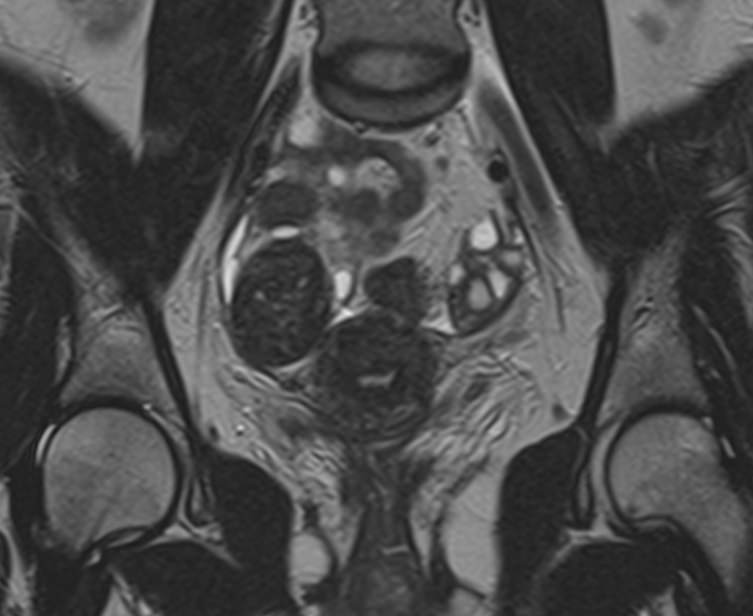

В клинике «Доступная медицина» магнитно-резонансная томография выполняется на высокопольном 32-канальном томографе последнего поколения TOSHIBA VANTAGE TITAN 1,5 Тесла, который обладает высокой разрешающей способностью и обеспечивает непревзойденное качество изображений. Аппарат производит сканирование в трех взаимоперпендикулярных плоскостях и послойными срезами с шагом от 1 мм, что позволяет визуализировать структуру органов и тканей малого таза в мельчайших подробностях. Точная и достоверная информация позволяет выявлять различные заболевания на начальной стадии, от чего напрямую зависит успех лечения.

С помощью данного исследования можно получить детальное послойное изображение матки, яичников, мочевого пузыря и мочеотводящих путей, а также жировой клетчатки, окружающей органы, и лимфатических узлов.

МРТ-сканирование органов малого таза позволяет выявить:

• Эндометриоз и эндометриоидные кисты яичников;

• Изменение формы и положения матки (двурогая матка, патологический загиб матки, гипоплазия);

• Изменения в маточных трубах (кровоизлияния, новообразования и врождённые аномалии развития), яичниках и шейке матки;

• Миоматозные узлы, полипы и новообразования в матке;

• Сужения или обструкцию (закупорку) мочеточника, изменения уретры (мегауретер и т.д.);

• Изменения лимфатических узлов и жировой клетчатки, распространение метастазов в них;

• Поражения мочевого пузыря (эндометриоидную ткань, новообразования и др.);

• Заболевания прямой кишки (опухоли, свищи).